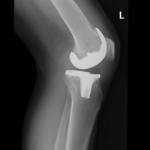

The goal of total knee replacement surgery is to relieve pain and restore the alignment and function of your knee.

The surgery is performed under spinal or general anesthesia. Your surgeon will make an incision in the skin over the affected knee to expose the knee joint. Then the damaged portions of the femur bone are cut at appropriate angles using specialized jigs. The femoral component is attached to the end of the femur with or without bone cement. The surgeon then cuts or shaves the damaged area of the tibia (shinbone) and the cartilage. This removes the deformed part of the bone and any bony growths, as well as creates a smooth surface on which the implants can be attached. Next, the tibial component is secured to the end of the bone with bone cement or screws. Your surgeon will place a plastic piece called an articular surface between the implants to provide a smooth gliding surface for movement. This plastic insert will support the body’s weight and allow the femur to move over the tibia, similar to the original meniscus cartilage. The femur and the tibia with the new components are then put together to form the new knee joint. To make sure the patella (knee cap) glides smoothly over the new artificial knee, its rear surface is also prepared to receive a plastic component. With all the new components in place, the knee joint is tested through its range of motion. The entire joint is then irrigated and cleaned with a sterile solution. The incision is carefully closed, drains are inserted and a sterile dressing is placed over the incision.